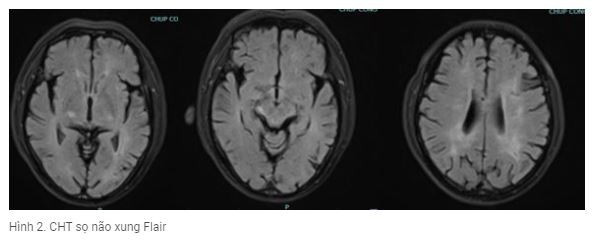

Kết quả CHT sọ : tổn thương tăng tín hiệu trên xung khuyết tán tổn thương chủ yếu vùng vỏ não thùy chẩm, đỉnh 2 bên ( hình 1); trên xung Flair tổn thương tăng tín hiệu vùng cuống não phải, dưới đồi phải, tổn thương chất trắng cạnh não thất 2 bên ( Hình 2).

Kết quả chụp cộng hưởng từ não.

Sau 5 ngày điều trị lâm sàng bệnh nhân có cải thiện hơn hết loạn thần, còn rối loạn trí nhớ, trả lời còn lẫn lộn thiếu chính xác, cơn co giật được kiểm soát, bệnh nhân được chụp lại CHT sọ não đánh giá tổn thương và xét nghiệm dịch não tủy lần 2 kết quả tổn thương trên flair không thay đổi, nhưng tổn thương mới trên DWI hiện rõ ràng hơn; protein dịch não tủy 0,84 g/l; tế bào : 03 tế bào .